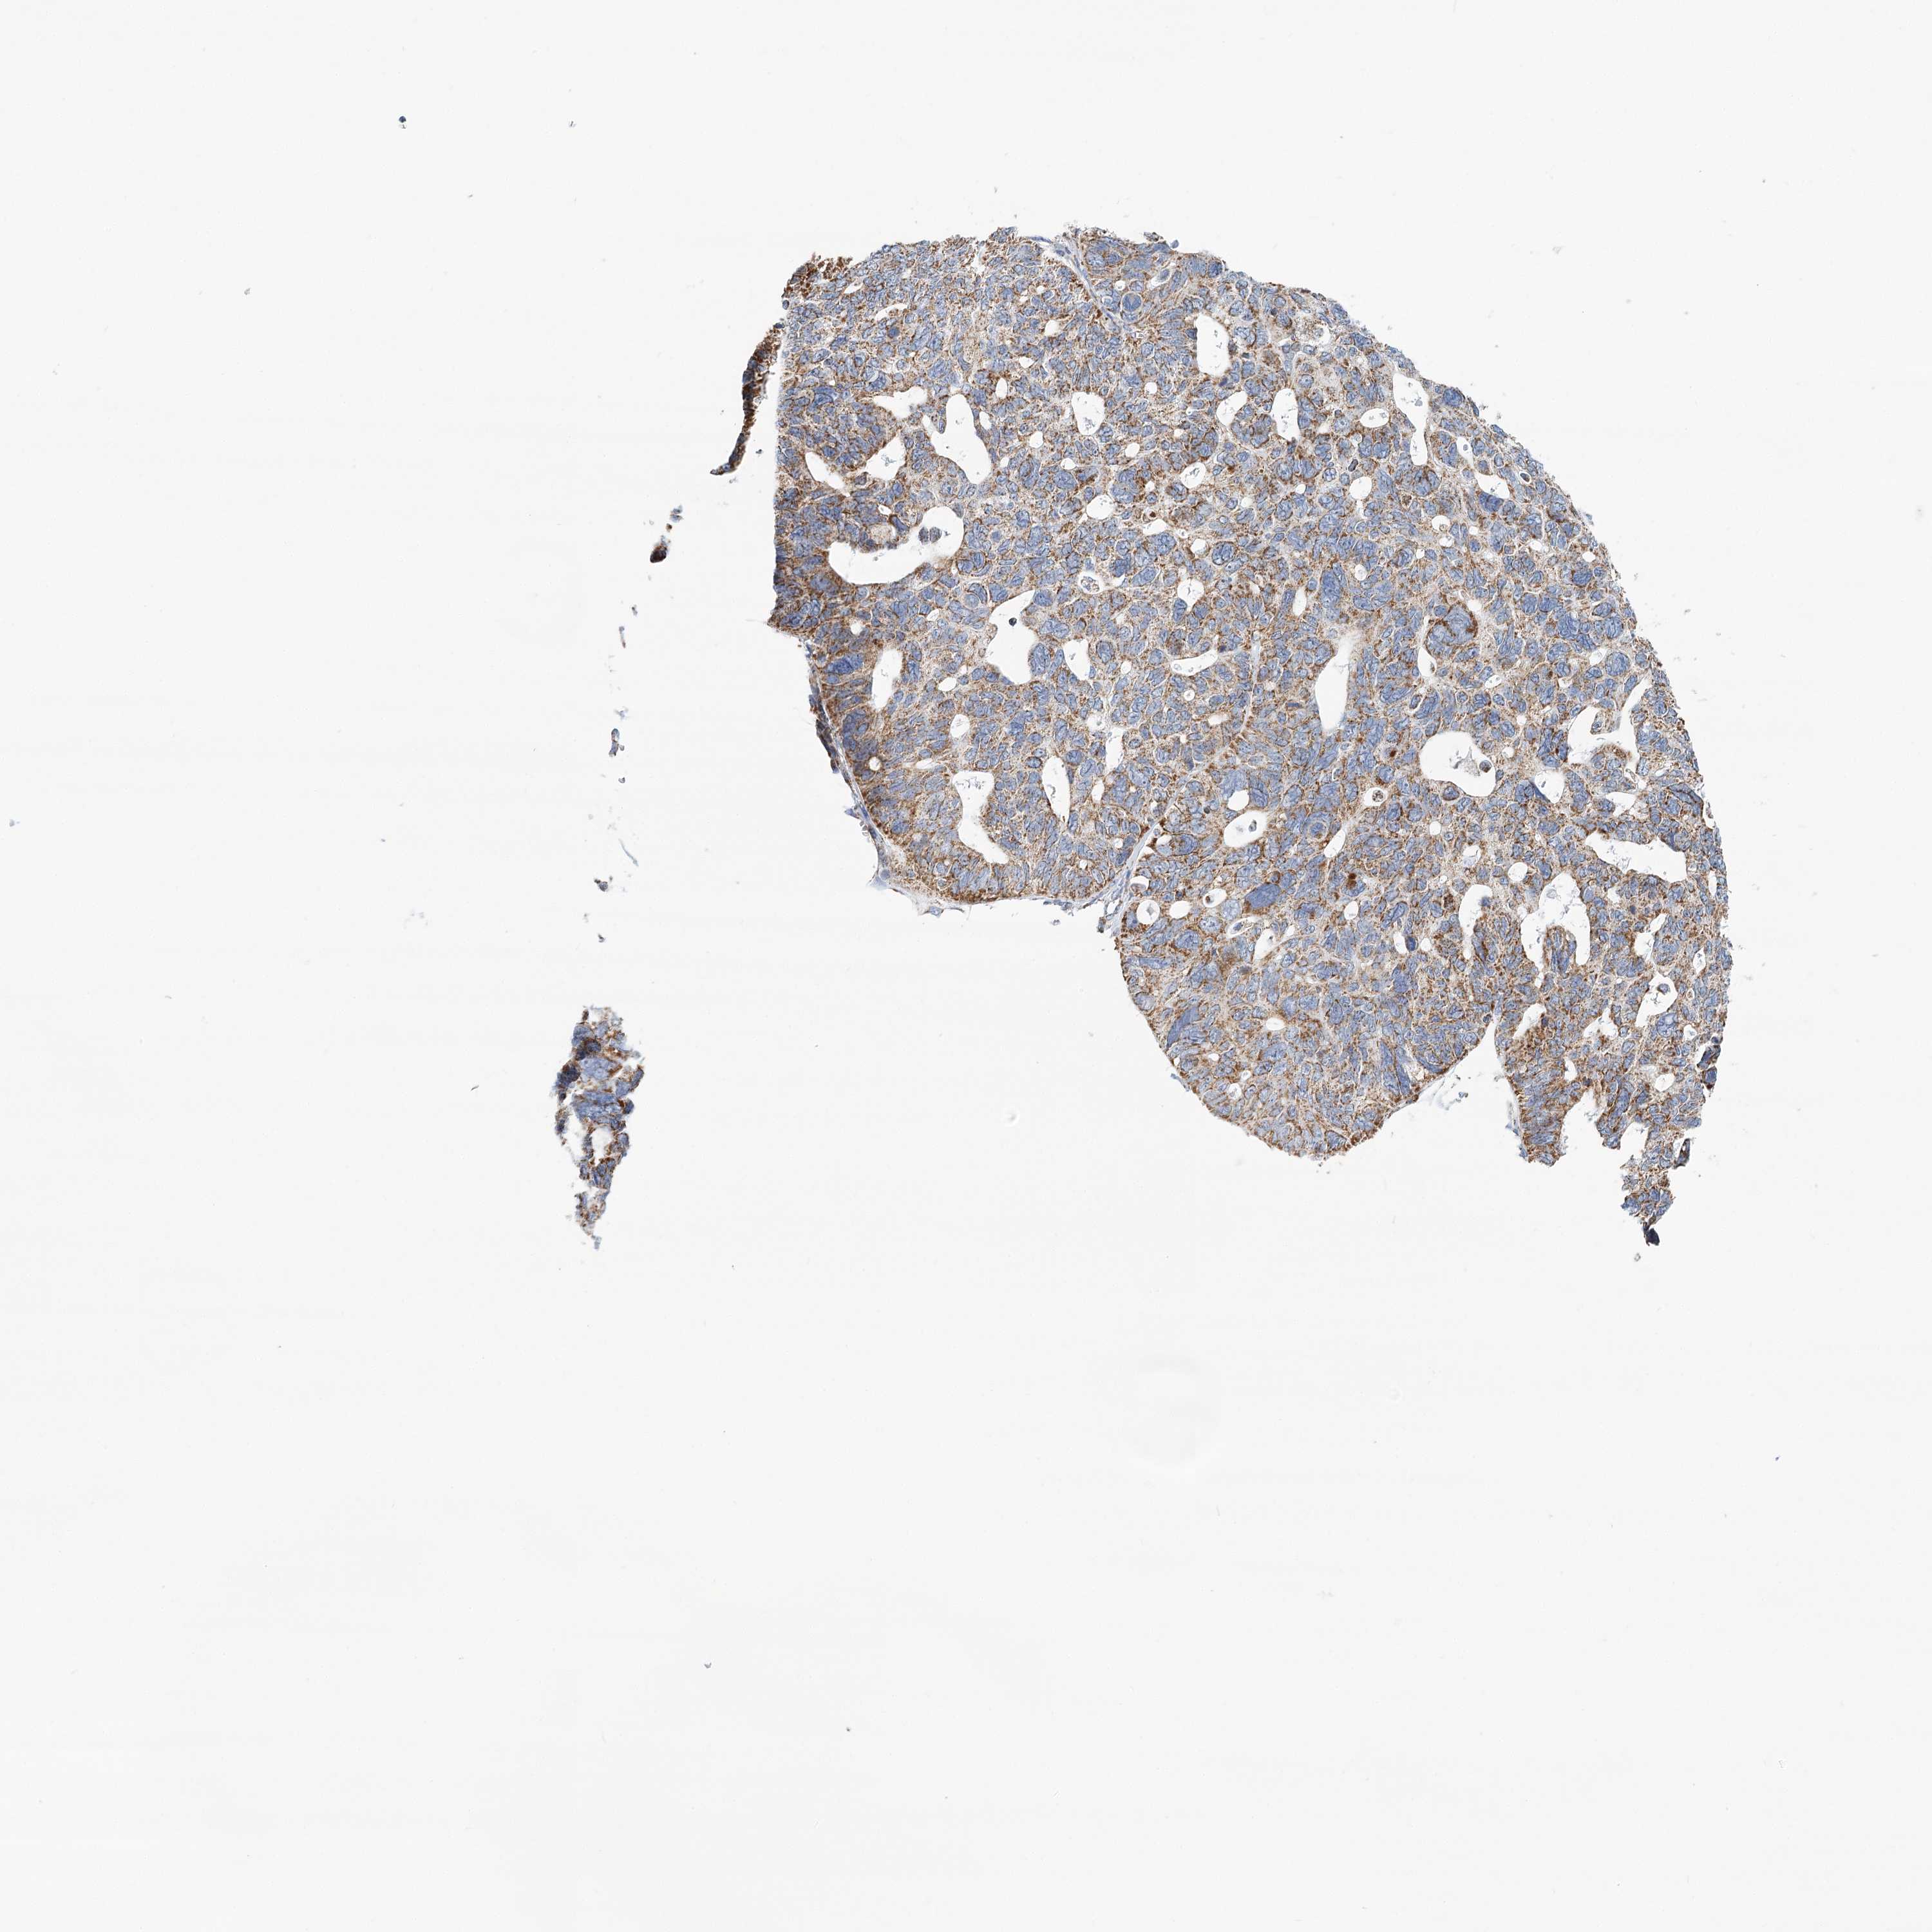

OVARIAN CANCER - Protein expressioni

A mouse-over function shows sample information and annotation data. Click on an image to view it in a full screen mode. Samples can be filtered based on level of antibody staining by selecting one or several of the following categories: high, medium, low and not detected. The assay and annotation is described here.

Note that samples used for immunohistochemistry by the Human Protein Atlas do not correspond to samples in the TCGA dataset.

Antibody stainingi

Antibody staining in the annotated cell types in the current human tissue is reported as not detected, low, medium, or high, based on conventional immunohistochemistry profiling in selected tissues. This score is based on the combination of the staining intensity and fraction of stained cells.

Each image is clickable and will lead to virtual microscopy that enables deeper exploration of all samples and also displays staining intensity scores, fraction scores and subcellular localization as well as patient and tissue information for each sample.

Antibody HPA032060

Antibody HPA032062

Antibody CAB034116

Staining

High

Medium

Low

Not detected

Intensity

Strong

Moderate

Weak

Negative

Quantity

>75%

75%-25%

<25%

None

Location

Nuclear

Cytoplasmic/membranous

Cytoplasmic/membranous,nuclear

Cystadenocarcinoma, serous, NOS

Carcinoma, endometroid

Cystadenocarcinoma, mucinous, NOS

Carcinoma, NOS